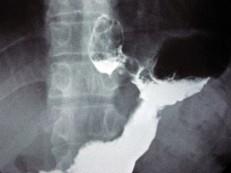

问题 男,56岁,胸骨后不适3月,吞咽时异物感,X线检查如图,最可能的诊断是()

选项 A.食道癌 B.食道腺瘤 C.贲门腺癌 D.胃癌 E.食道下段溃疡

答案 C